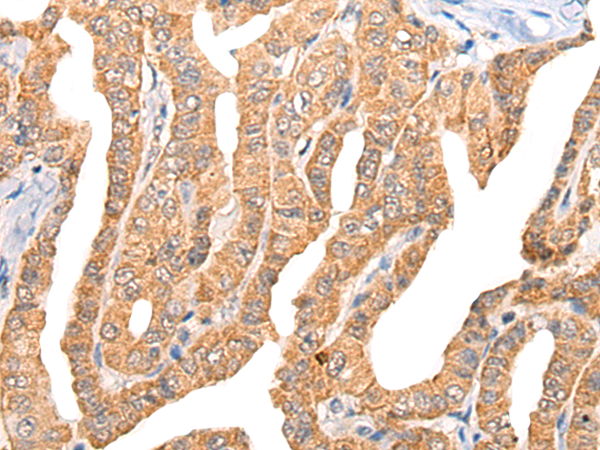

IHC positive control: |

Human thyroid cancer and Human liver cancer |

IHC Recommend dilution: |

25-100 |